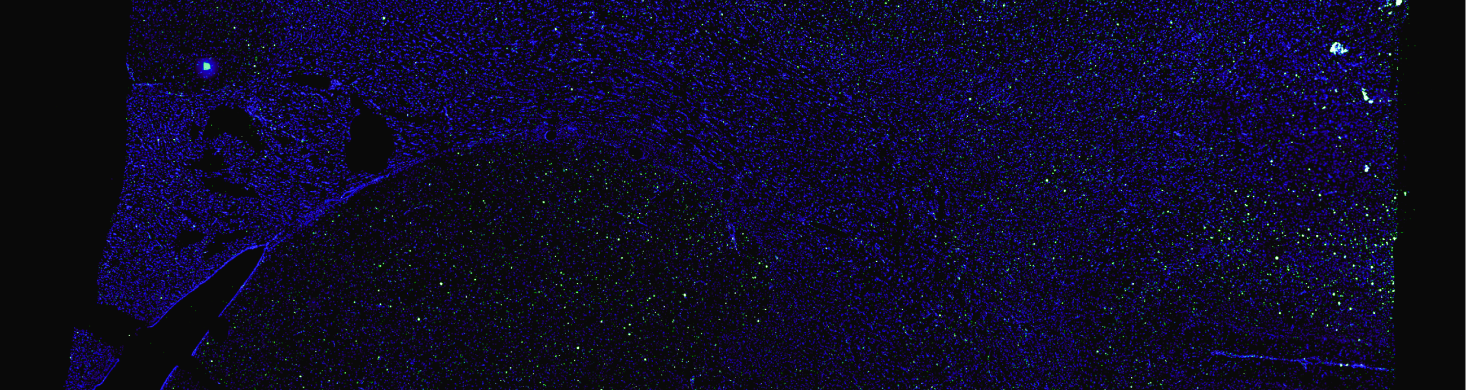

Launched in 2026, the Dyno-yp2 is a top-performing capsid that achieves both exceptional brain transduction and significant liver detargeting in TfR-humanized mice.

Launched in 2025, the Dyno-ahq vector is optimized for widespread IV delivery to the brain, with exceptional liver detargeting and a highly conserved mechanism for blood-brain barrier crossing.

Launched in 2023, the Dyno-hc9 vector (aka bCap 1) was the first Dyno brain capsid optimized for highly efficient pan-brain delivery across the blood-brain barrier, with broad CNS tropism and liver detargeting.